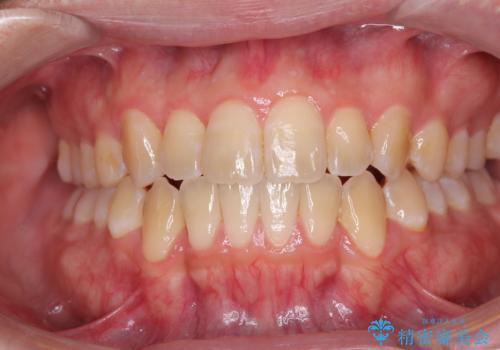

【審美装置】前歯で噛めない!抜歯しないで治したい

MARPEで非抜歯矯正|オープンバイトと八重歯を改善